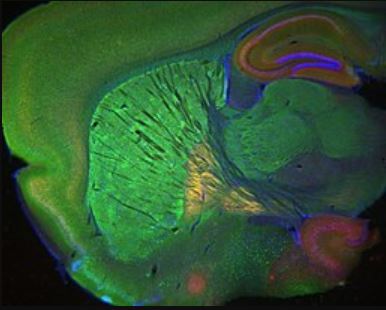

What exactly is the endocannabinoid system? This huge network of receptors is at the cellular level. It is found throughout the body. There are cannabinoid receptors found in the brain- but they are also throughout the organs, skin, bones and our connective tissues.

According to UCLA, scientists confirm that this system is in basically all our parts:

“the receptors are present throughout the body, including our skin, immune cells, bone, fat tissue, liver, pancreas, skeletal muscle, heart, blood vessels, kidney, and gastrointestinal tract. We now know the endocannabinoid system is involved in a wide variety of processes, including pain, memory, mood, appetite, stress, sleep, metabolism, immune function, and reproductive function.Endocannabinoids are arguably one of the most widespread and versatile signaling molecules known to man.”